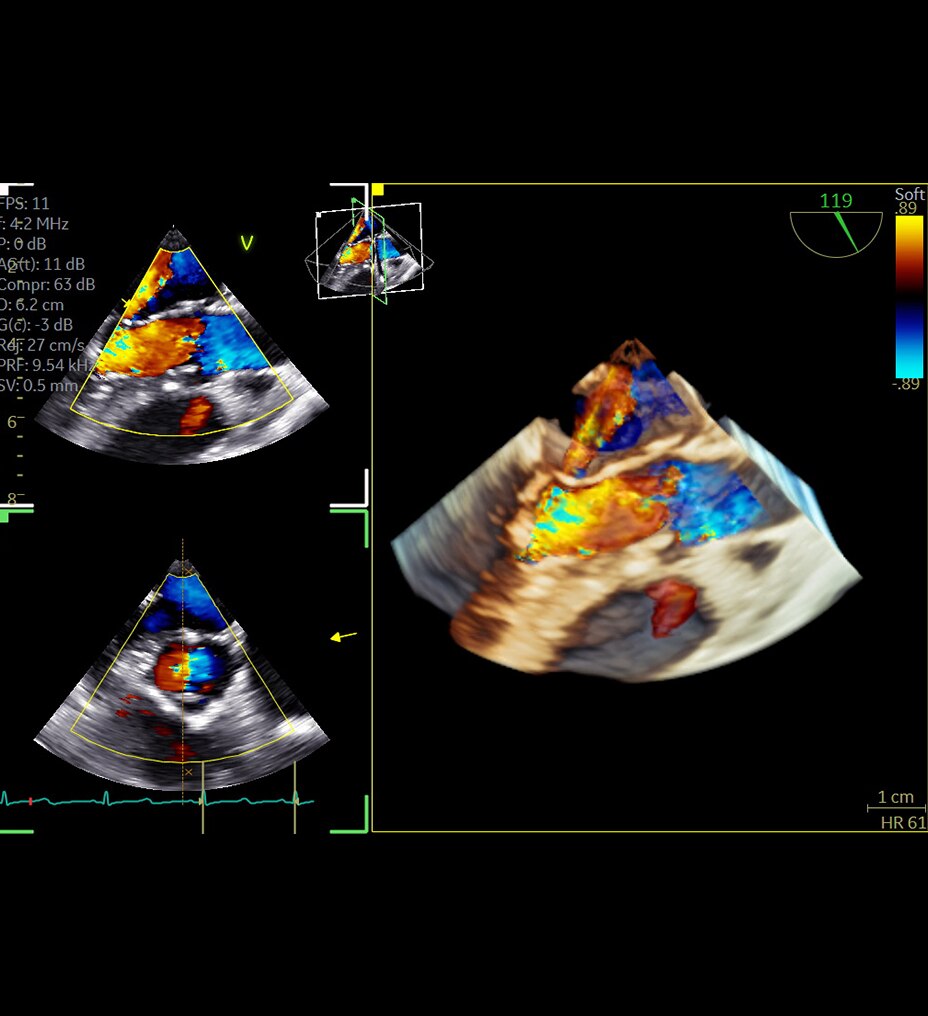

SIGNA™ Champion offre un design modulare con opzioni software e hardware pronte per soddisfare le priorità cliniche. Include strumenti di base e avanzati e soluzioni per la qualità delle immagini come AIR™ Recon DL e Sonic DL™. Queste applicazioni consentono non solo di ottimizzare i casi di routine, ma anche di operare in altri campi specifici come neurologia, apparato muscolo-scheletrico, cardiologia e oncologia. E non è tutto. SIGNA™ Champion è in grado di offrire configurazioni a 32, 48 e 64 canali per garantire la massima flessibilità e semplificare la configurazione delle bobine sulla base delle diverse anatomie.